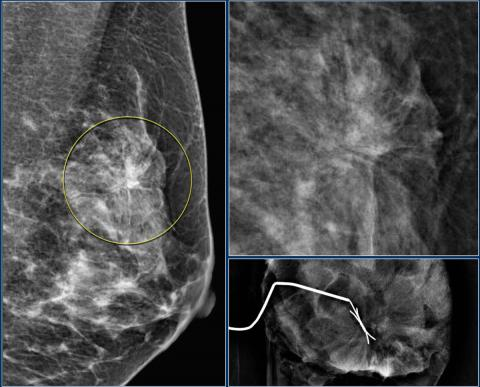

- Marge: Bien délimitées, Obscure, Microlobué, Mal délimitée, Spiculée

- Spiculée (très suspect)

- Spiculé, irrégulier de forte densité

- Masse irrégulière spiculée avec calcifications pléomorphe